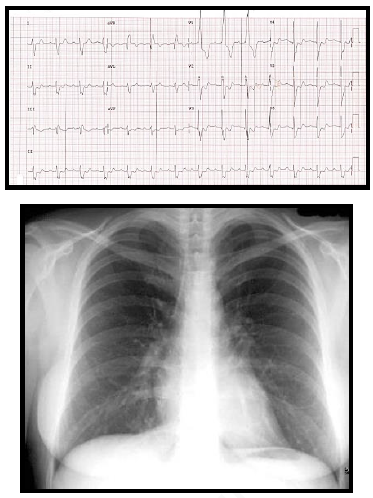

Paciente de 34 anos, G3P1A2, no décimo dia de puerpério, deu entrada no pronto socorro com queixa de dor torácica associada a dispneia importante. Ao exame físico apresenta regular estado geral, corada, hidratada, afebril, ausculta pulmonar sem alterações, taquipneia (frequência respiratória de 30 ipm) com saturação de oxigênio de 84% em ar ambiente, ausculta cardíaca sem alterações, frequência cardíaca de 108 bpm e pressão arterial de 86 x 54 mmHg. O eletrocardiograma e o RX de tórax estão demonstrados nas figuras abaixo. Os exames laboratoriais demonstram Troponina = 0,9 mcg/dl (Valor normal < 0,01 mcg/dl) e Peptídeo Natriurético Cerebral (NT pró-BNP) = 1314 pg/dl (Valor normal < 200 pg/dl).

enunciado 540559-1

Sobre o diagnóstico mais provável, assinale a alternativa correta.